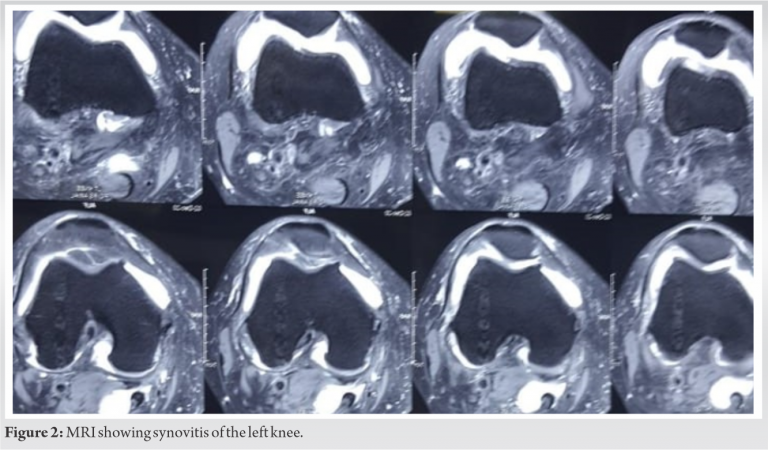

A 50-year-old woman came with chief complaints of pain and swelling in the left knee. She had a recent history of twisting injury while walking. Physical examination revealed tenderness along the lateral joint line and McMurray’s test was positive for lateral meniscus. Flexion was terminally restricted and painful. Radiographs showed evidence of lateral compartment osteoarthritic changes. Tear of lateral meniscus (Fig. 1) along with synovitis (Fig. 2) and degenerative changes in the cartilage were evident on magnetic resonance imaging (MRI) of the left knee. Arthroscopic partial meniscectomy was planned on the basis of her clinical and radiological presentation.